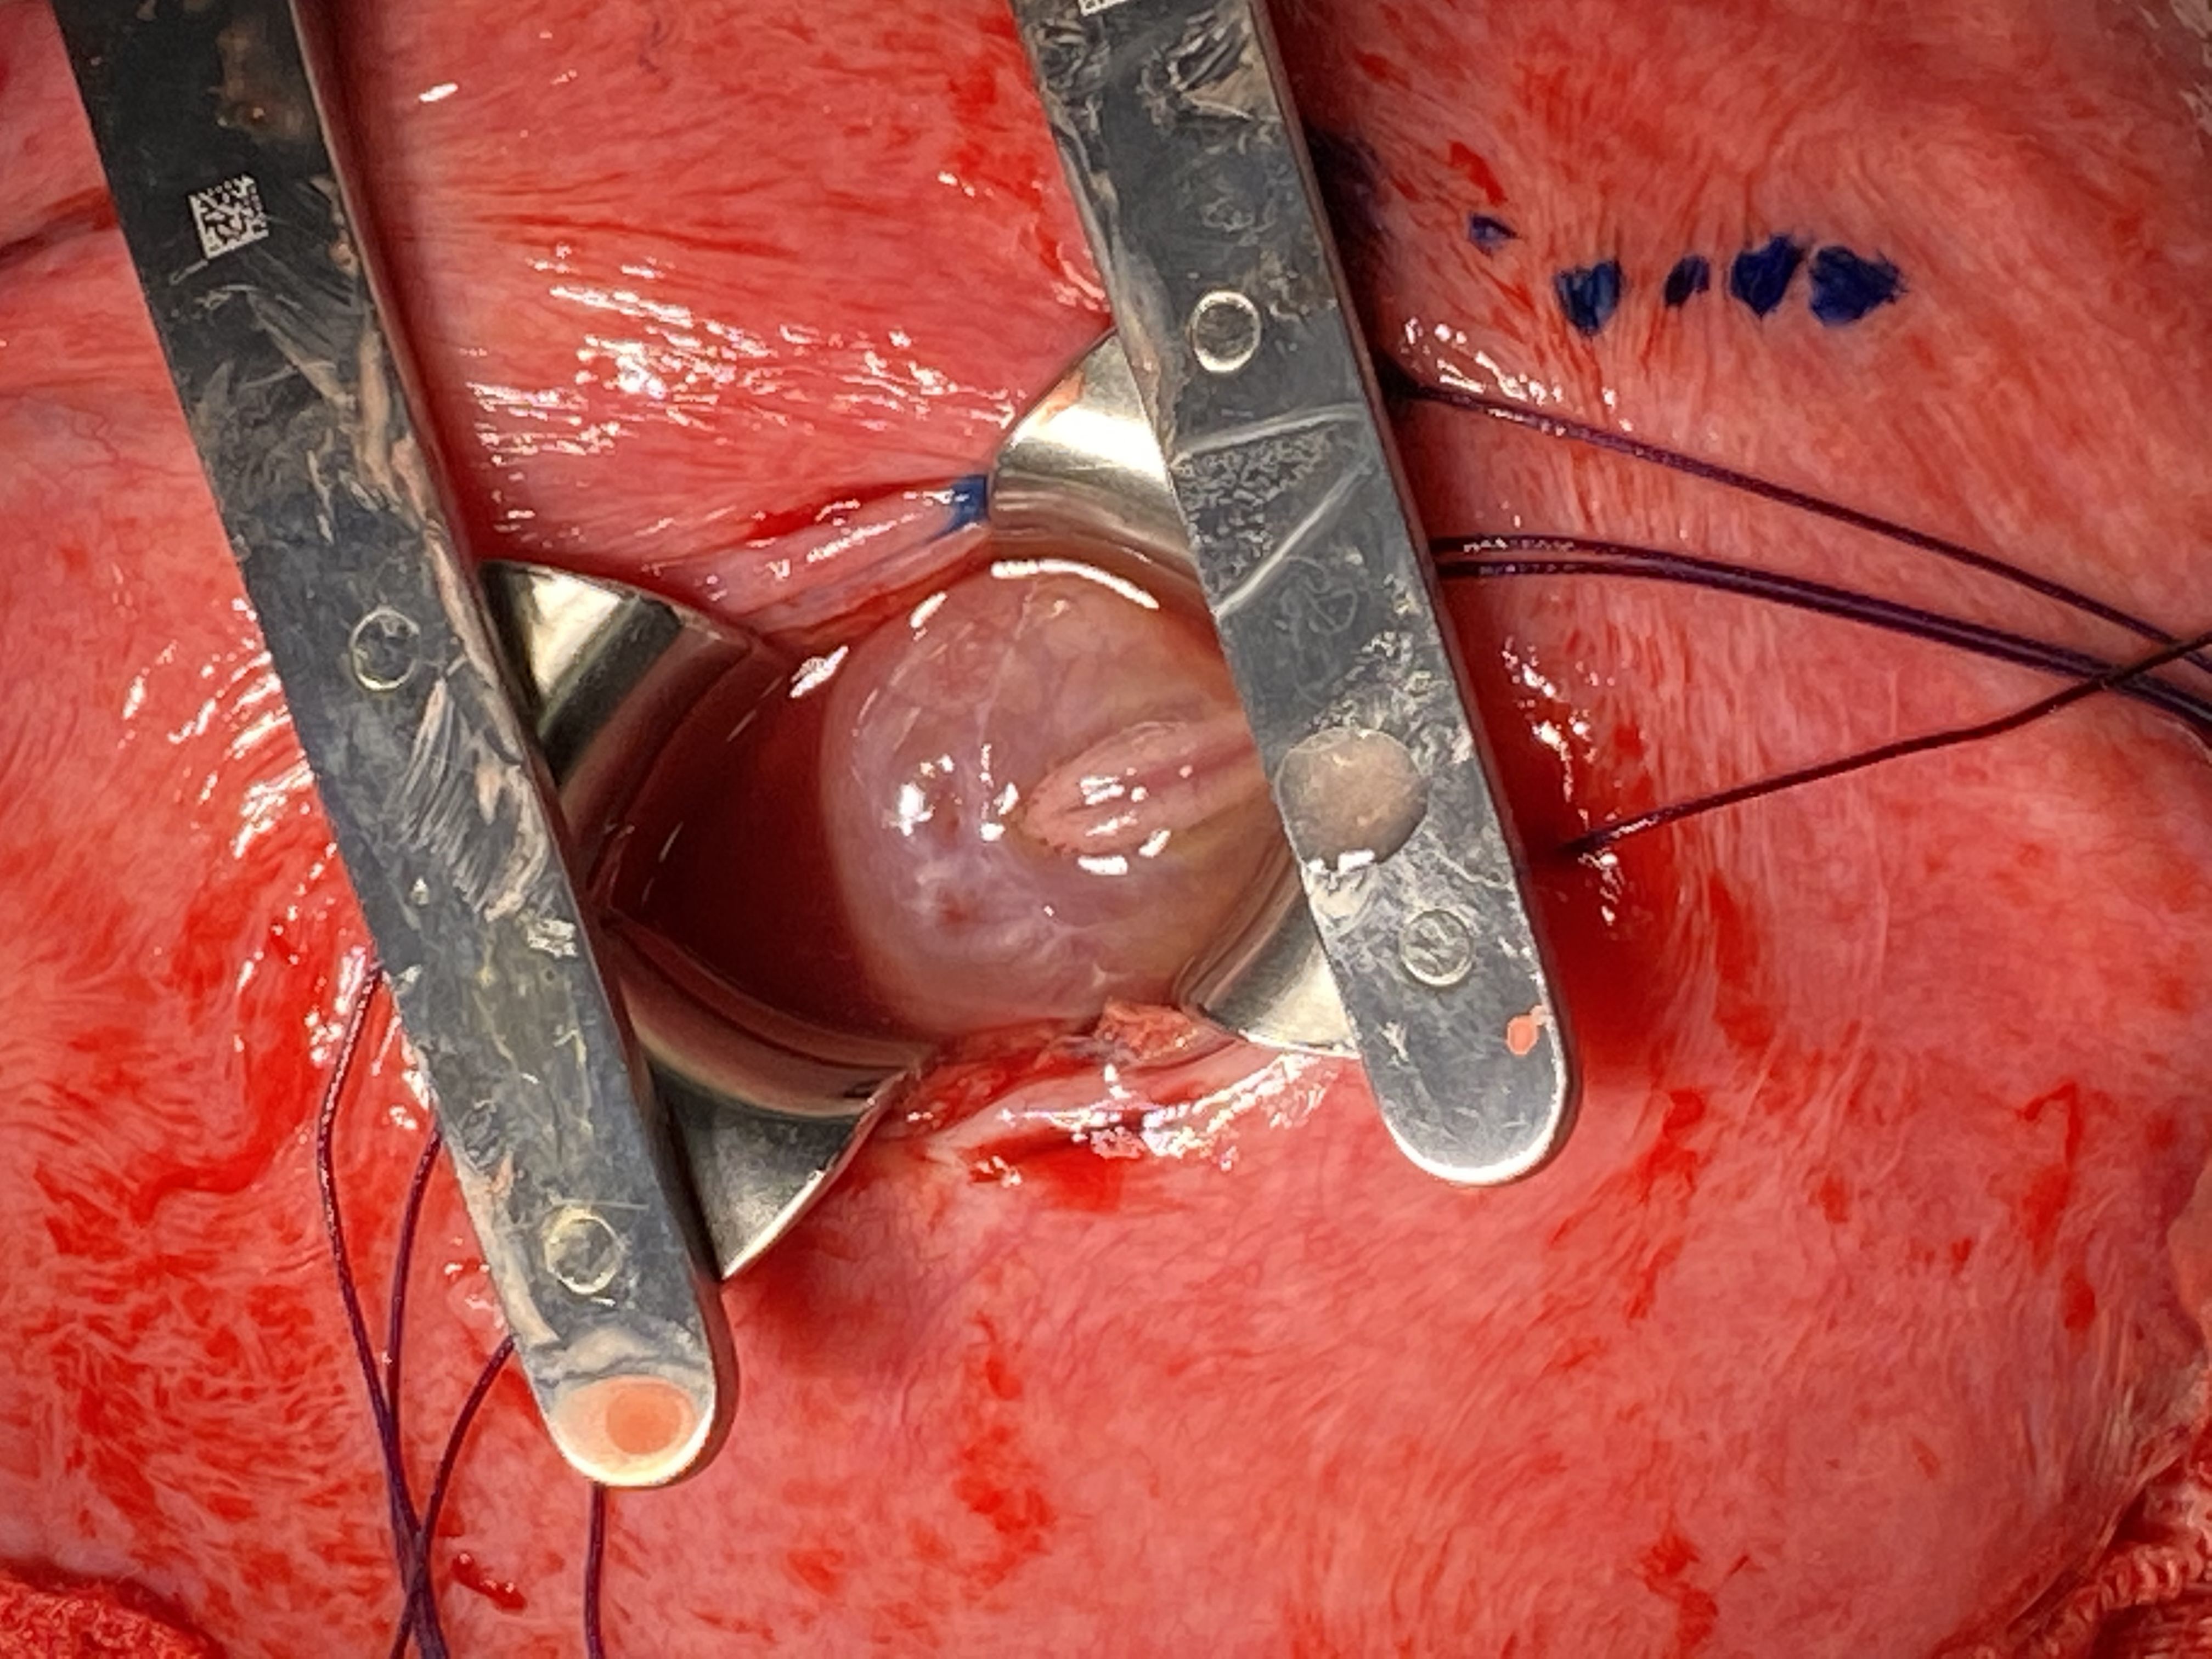

Nosso serviço, sob a coordenação do Dr. Fábio Batistuta, realiza a cirurgia de correção intraútero da mielomeningocele pela técnica da cirurgia aberta com minihisterotomia, desenvolvida pelo Dr. Fábio Peralta.

![]()

Equipe de Cirurgia Fetal da Fetali, sob a coordenação do Dr. Fábio Batistuta de Mesquita em campo na correção intrauterina da mielomeningocele.

Correção intrauterina da mielomeningocele por minihisterotomia: À esquerda, observa-se a mielomeningocele exposta na incisão uterina (minihisterotomia). À direita, a incisão no útero fechada com aproximadamente 3 cm de tamanho.